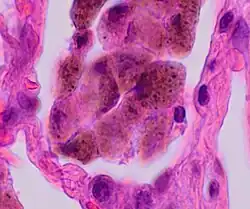

A "smoker's macrophage", with yellow to light brown and finely granular cytoplasmic pigment.

Histopathology of smoker's macrophages with anthracotic stippling, indicating the presence of both respiratory bronchiolitis and anthracosis.